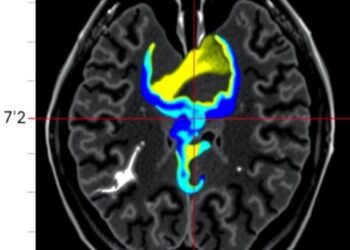

In a groundbreaking study published in the journal Pediatr Radiol, researchers are shedding light on a relatively underexplored aspect of ...